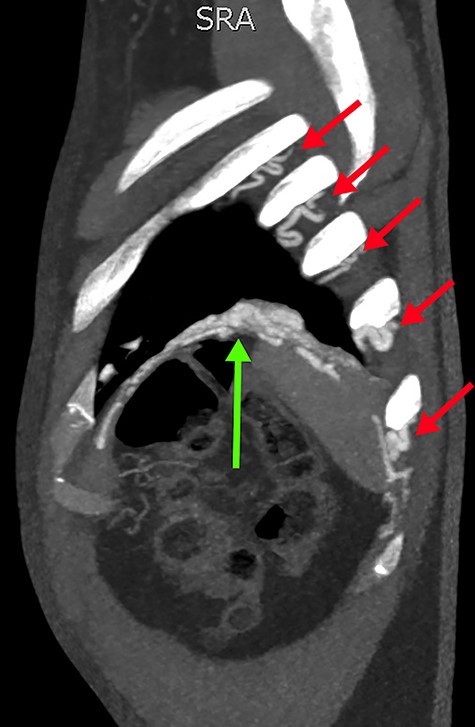

Sagittal slice from the CTPA, demonstrating tortuous intercostal arteries (red arrows) heading towards and feeding the PAVM in the left lung’s lower lobe (green arrow).

Concerned for pulmonary embolism (PE), a computed tomography pulmonary angiogram (CTPA) was arranged. PE was excluded; however, it did reveal a complex left-sided intra- and extrathoracic vascular malformation within the anteromedial segment of the left lung’s lower lobe, the lingula segment, the subdiaphragmatic space and the left chest-wall (Figs. 1 and 2). The arterial supply derived from large tortuous vessels arising from a combination of the coeliac trunk, six posterior intercostal arteries and the left inferior phrenic artery (Fig. 3). It then communicated with the left upper and lower lobe subsegmental pulmonary arteries, and the left lower lobe pulmonary vein. Subsequent echocardiography was normal, with no significant valvular pathology—evidencing that the pansystolic murmur was an arteriovenous bruit.